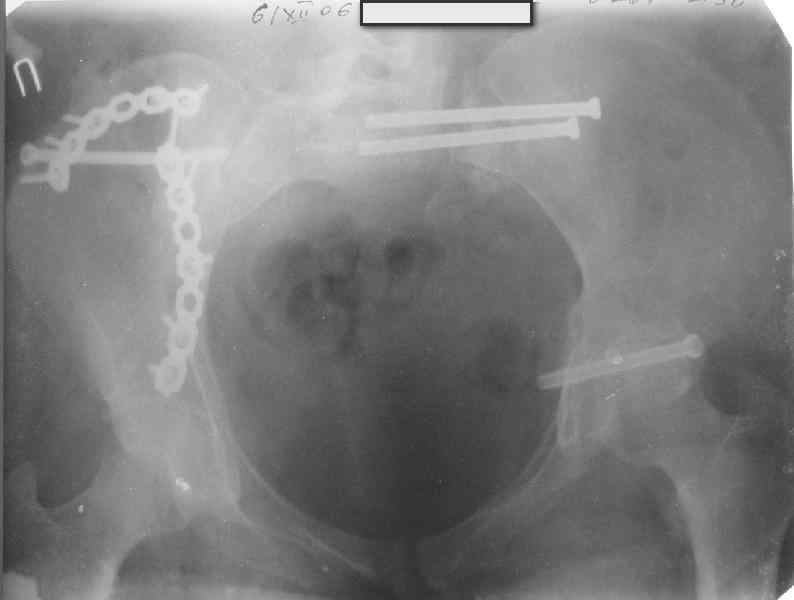

Здравствуйте, коллеги. Какие будут мнения по поводу лечения представляемой больной?

Молодая девушка 19 лет, травма 1 год назад, тогда же прооперирована.

В настоящее время имеются ноющие боли в области крестца слева, нарушение походки, ощущение неуверенности, слабости в левой нижней конечности, неврологически -непостоянные парестезии в левой нижней конечности. Ходит с дополнительной опорой, страдает от ожирения.

Какова по вашему будет оптимальная тактика в отношении несращения крестца? Замена винтов на более длинные с коррекцией их положения+ туннелизация зоны нестращения, открытое вмешательство с костной аутопластикой или еще какие варианты?

В приложении снимки при поступлении и послеоперационные год назад.